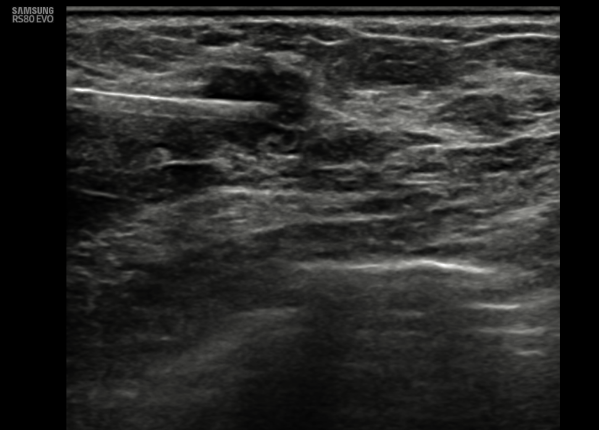

36 year old female comes with history of left breast lump. She is evaluated outside for same and HPR is papillary lesion. She comes to our hospital, we repeat her mammogram and USG, which is suggestive of a high density large mass with lobular margin in upper outer quadrant of left breast. As out side HPR is discordant with imaging finding, we repeat her biopsy and MRI. Repeat biopsy is suggestive of again papillary lesion. And MRI is suggestive of invasion of chest wall muscle. What do we do now?

Adenomyoepithelioma is a primary breast neoplasm of rare entity caused by proliferation of both epithelial and myoepithelial components, Benign to low grade malignant behavior and has a propensity for recurrence. Either epithelial or myoepithelial component can show malignant transformation so thorough evaluation recommended*. Overlap of histopathological features usually lead to misinterpretation as invasive carcinoma or intraductal papilloma or sclerosing adenosis. Complete wide excision with negative margins is standard treatment to prevent local recurrence. It is difficult to diagnose this on imaging alone, however familiarity with this rare entity to radiologist is essential to raise possibility.

Final histopathology was suggestive of Adenomyoepithelioma (AME). (Few foci of atypia were seen, however there was no malignancy)